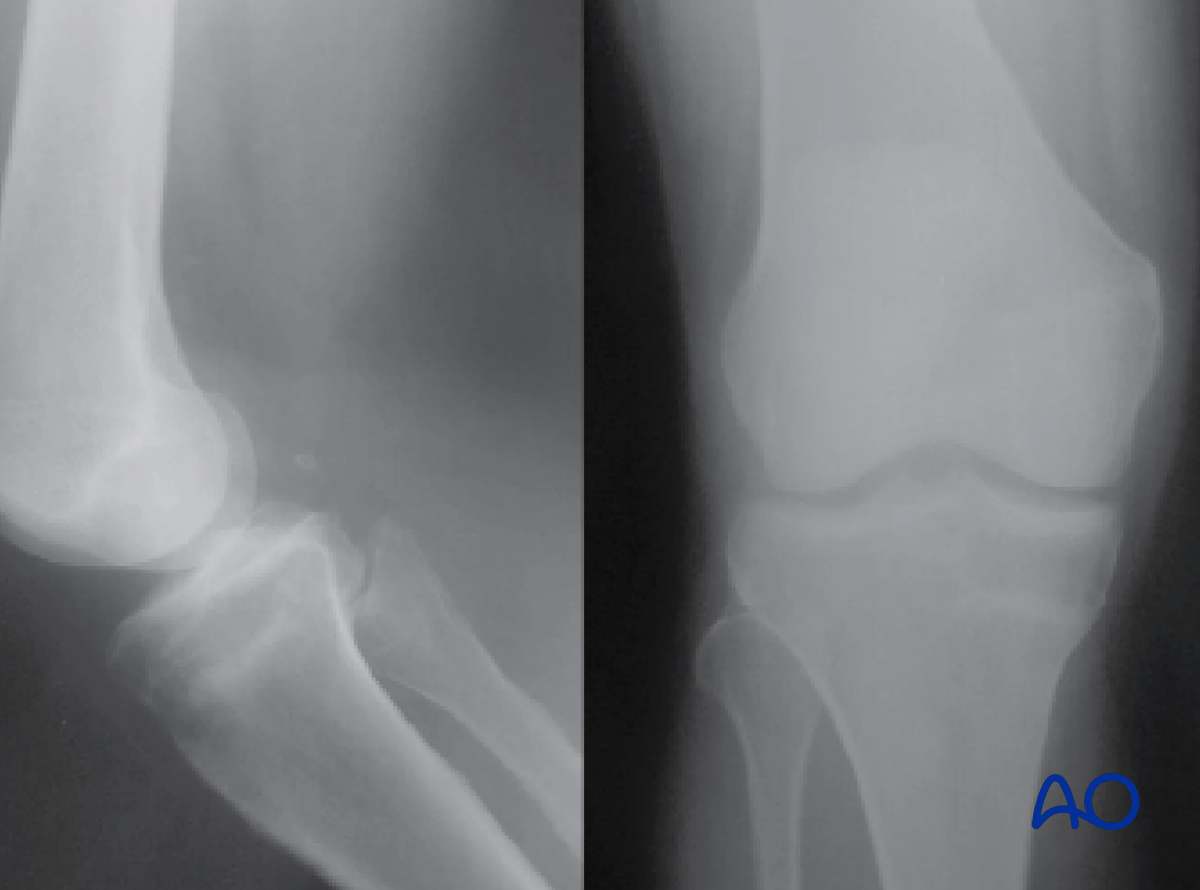

Proximal tibia: complete articular fracture - Angular stable plating

The medial plateau is the larger of the two articular surfaces and is concave in both transverse planes. The lateral plateau is smaller and convex and lies slightly higher than the medial joint surface, which helps in identifying it on the lateral x-ray.

Proximal tibia: anatomy